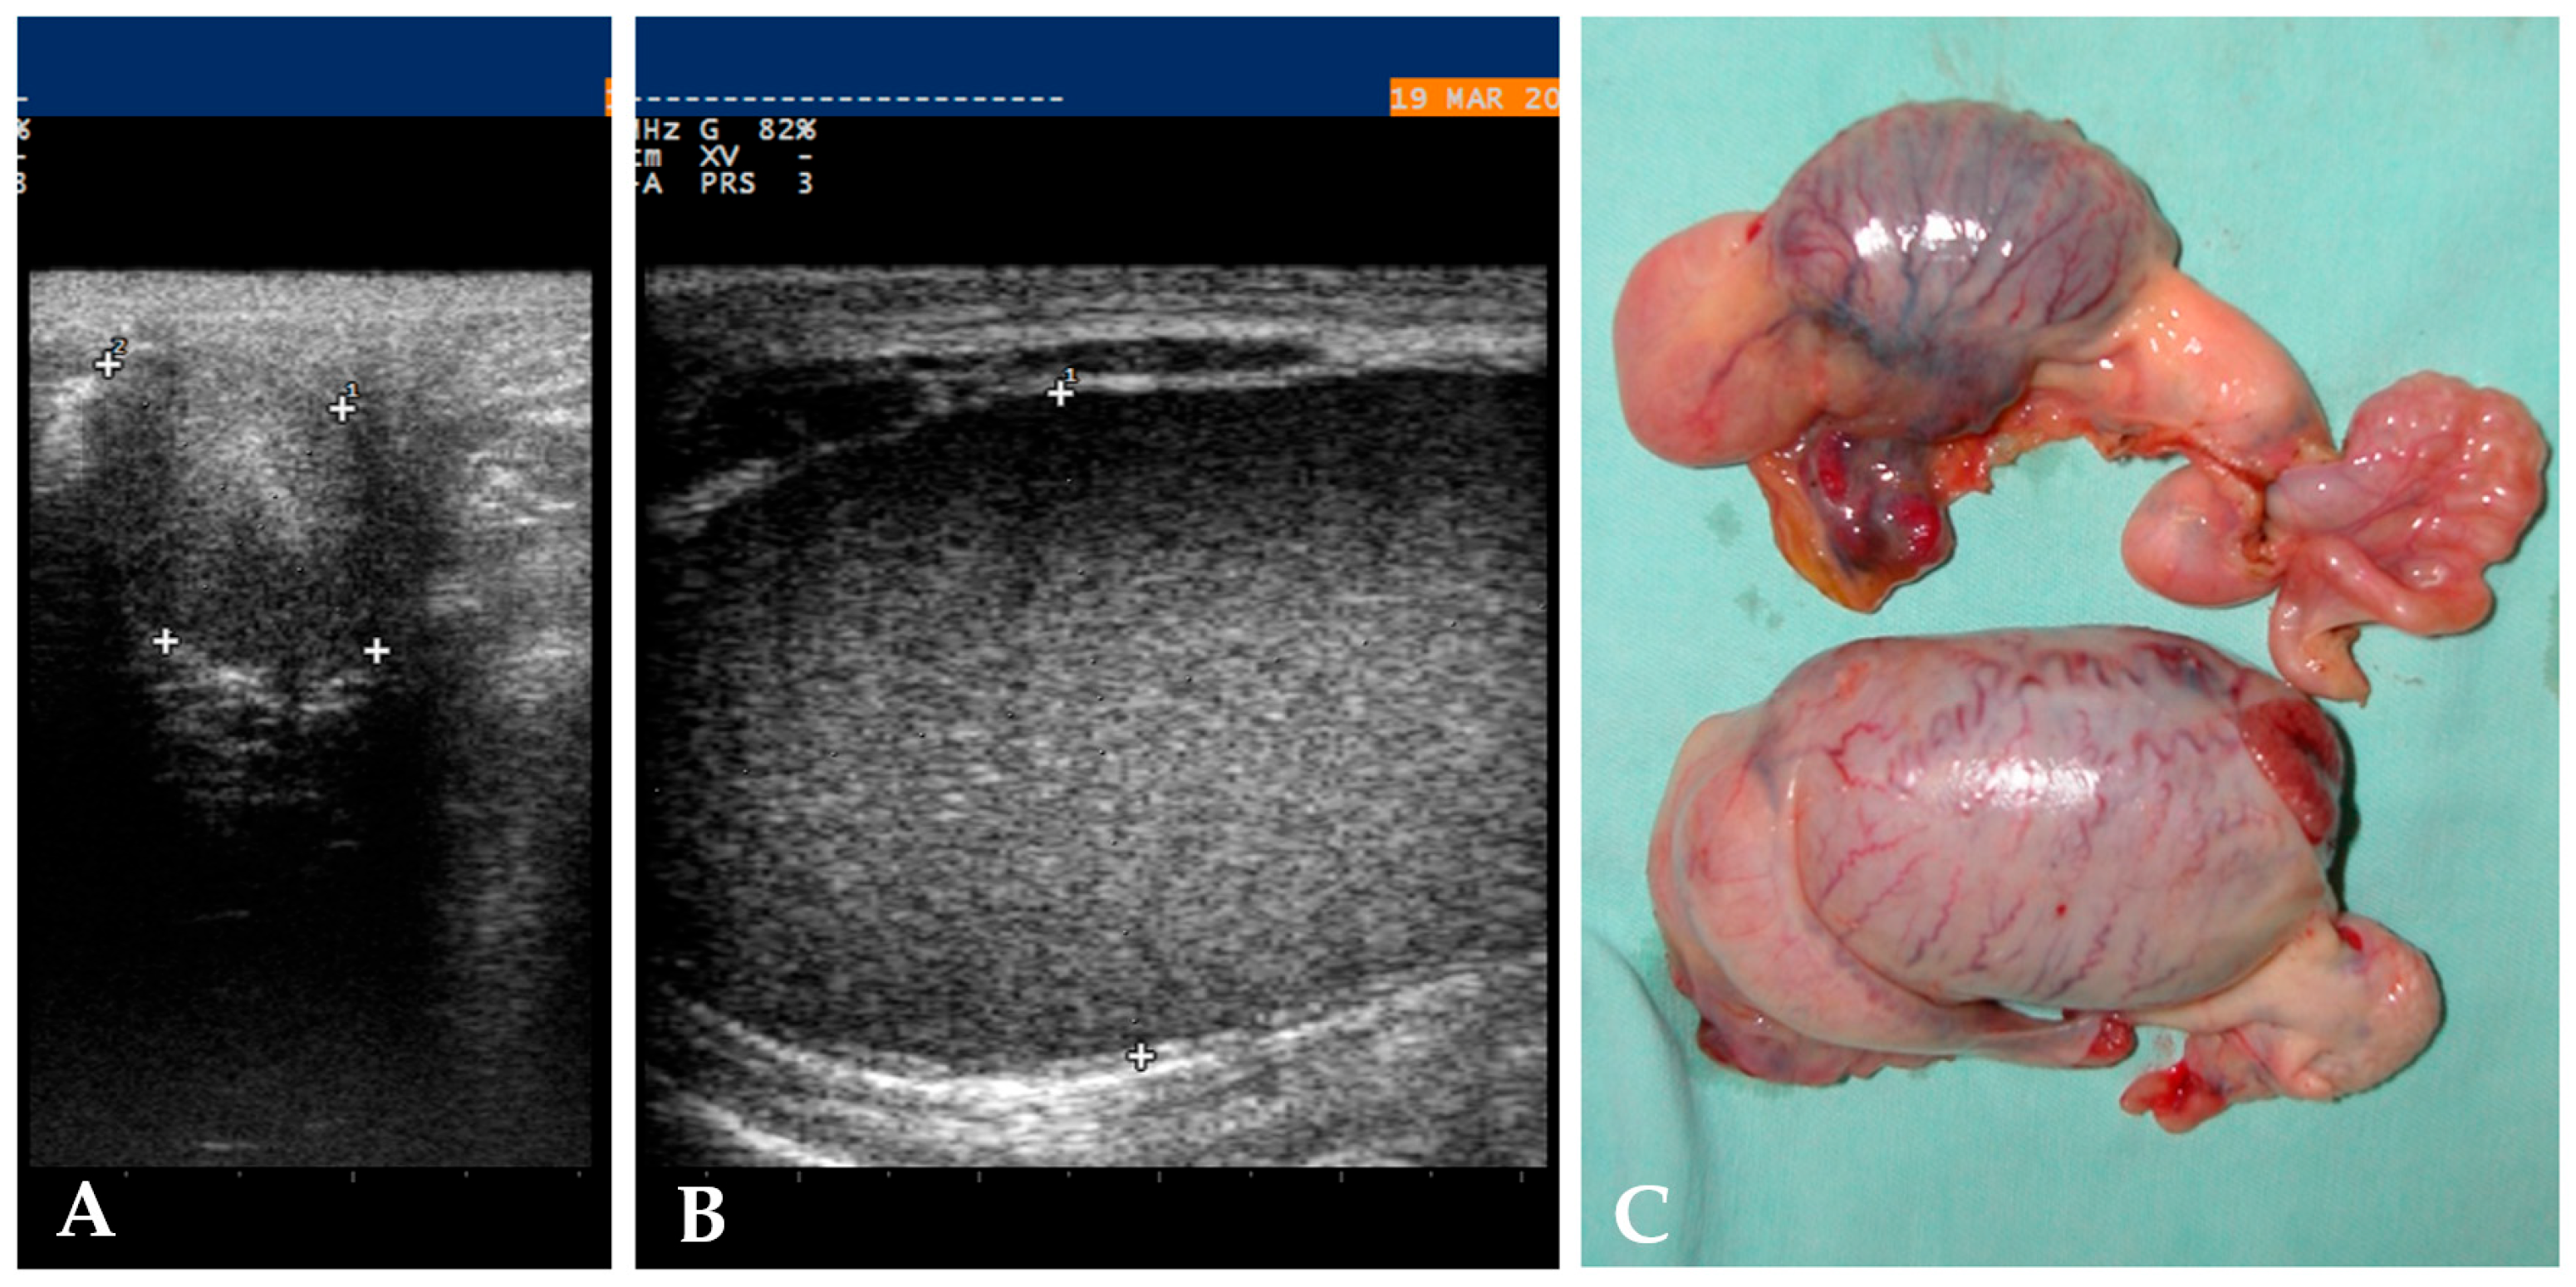

2.2. Diagnostics